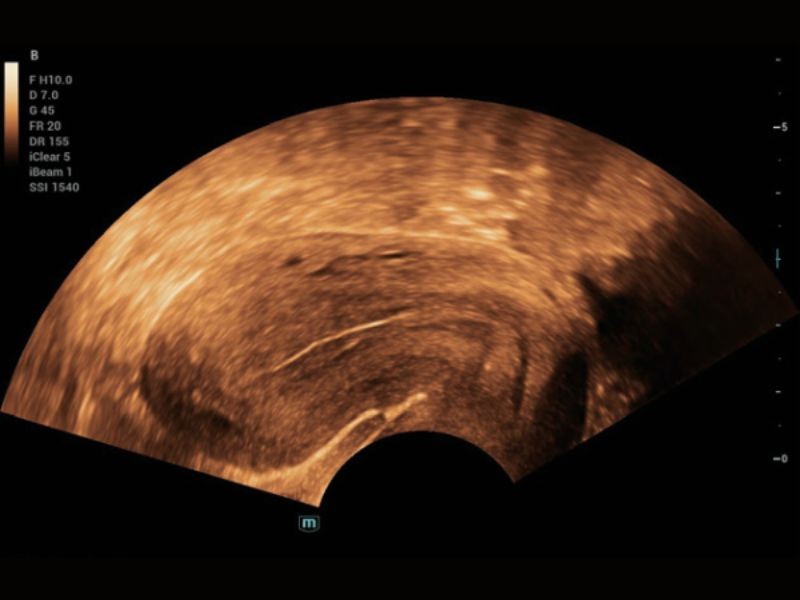

Solução de Imagem Geral

iToque⁺

Otimização de imagem dinâmica em tempo real